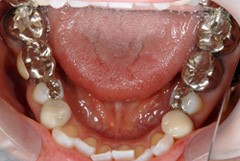

銀歯を白く

銀歯を白くしたいというお問い合わせも

多数頂くことがあります☆

見た目はもちろん、セラミックのかぶせ物は

汚れが付着しにくいので、虫歯へのリスクも少なくなります。

保険適用外にはなりますが、将来的なことや審美的なことを

考えると、セラミックのかぶせ物をおススメ致します。